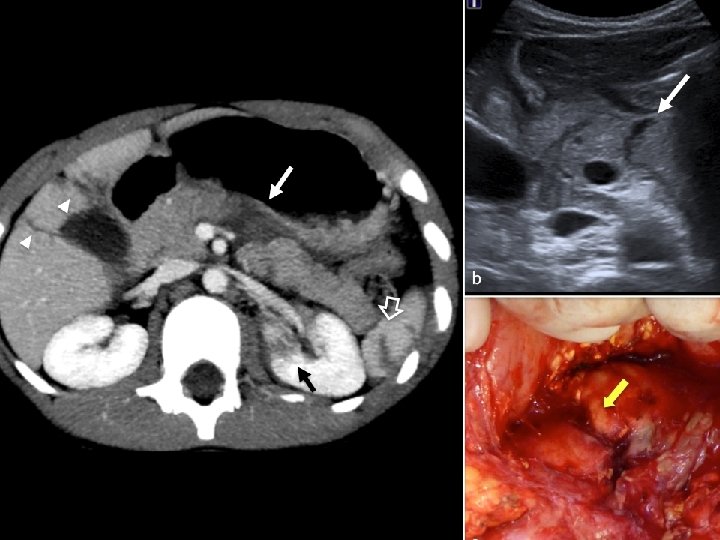

Disruptions of the Pancreatic Duct n Internal pancreatic fistula (pancreatic pseudocyst) – Represents 75% of cystic lesions of the pancreas – Electrolyte concentrations in the pseudocyst fluid are equivalent to those in plasma – Patients present most often with upper abdominal pain, early satiety, nausea and vomiting – An abdominal mass is present in less than half – Laboratory findings are nonspecific – CT scan of the abdomen is the favored study and initial assessment

Radiographic Evaluation n Abdominal ultrasound – May be of limited value due to the presence of air and fluid within the bowel overlying the pancreas – May detect pancreatic edema n CT scan – Currently the most widely accepted and sensitive method used to confirm the diagnosis n MRI – Holds great promise – Results are equal to that of CT scan

Chronic Pancreatitis n Diagnosis – Is usually suspected on clinical findings – Routine laboratory tests are rarely helpful – Radiographic evaluation may reveal pancreatic calcifications on plain films – CT scan is useful in evaluating the size and texture of the pancreas – Endoscopic retrograde pancreatography – Pancreatic endocrine function